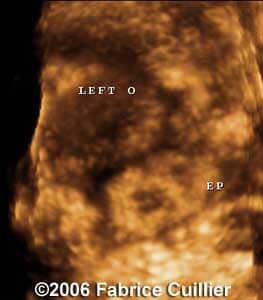

These are some cases of ectopic pregnancy (GEU) using the 2D and 3D scans.

Case 2